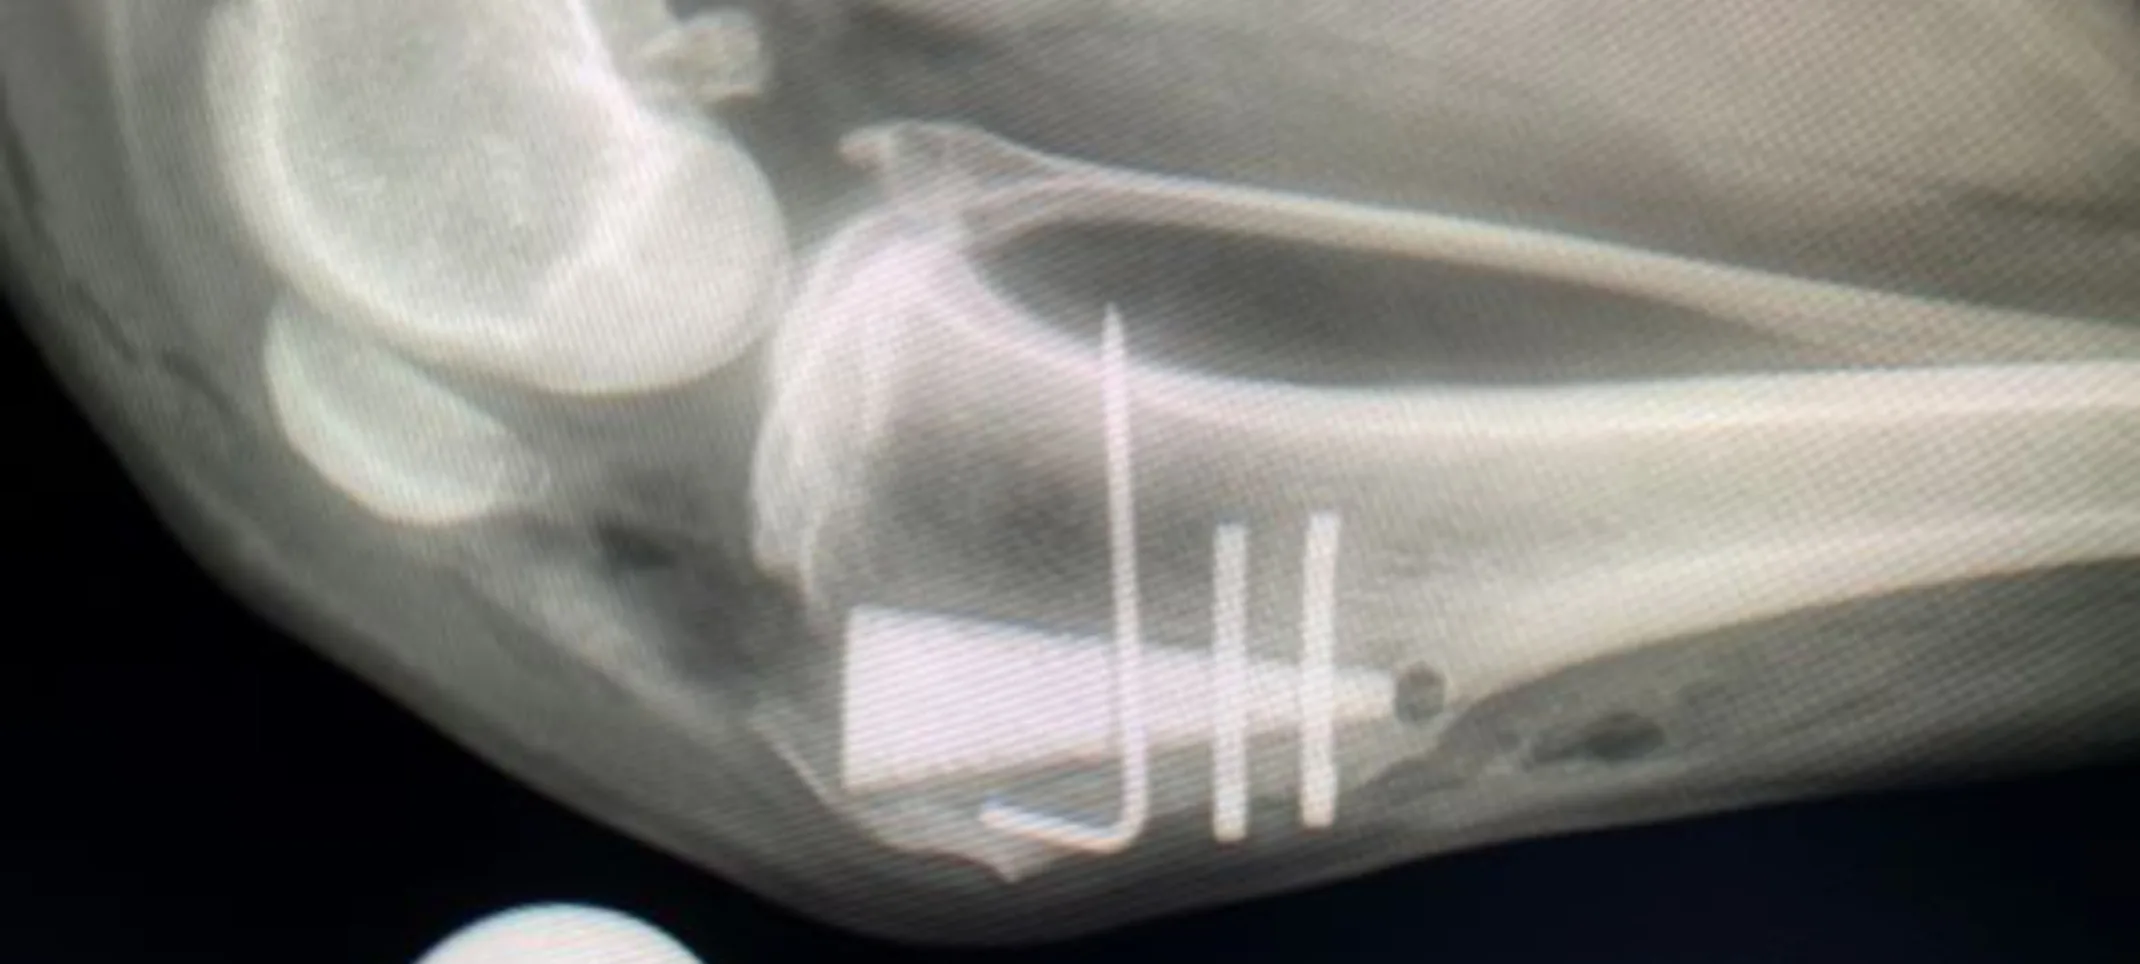

It provides advantages over previous TTA methods. It utilizes a titanium foam wedge implant to advance and support the tibial tuberosity. This implant is porous and both promotes ingrowth of bone and is resistant to bacterial growth. MMP TTA permits weight bearing immediately, with many patients bearing some weight immediately postoperatively.